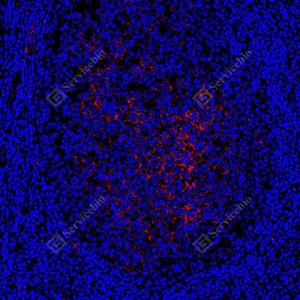

| IF检测CD14蛋白(货号 GB15254)(红色). 样品: 人扁桃体, 4%多聚甲醛 (货号G1101) 固定12-24小时. 抗原修复: 抗原修复仪(货号 ARI-4),Tris-EDTA抗原修复液(pH 9.0) (货号G1203), 水浴100℃, 25分钟. 封闭: 3% BSA(货号GC305010)的PBS溶液, 室温孵育30分钟. —抗: 1: 500稀释, 4℃ 孵育过夜. 二抗: Cy3标记山羊抗小鼠IgG (H+L) (货号GB21301), 1: 300稀释, 室温孵育1小时. |